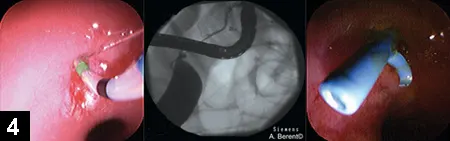

Figure 4. Endoscopic retrograde cholangiopancreatography in a canine patient during common bile duct stent placement

The major duodenal papilla can be visualized using a side-view duodenoscope and cannulated with a sphincterotome catheter. A guide wire can be advanced into the common bile duct under fluoroscopic guidance after retrograde cholangiogram–pancreatogram; a polyurethane or metallic stent is advanced over the wire into the common bile duct via endoscopy–fluoroscopy, transverses the major duodenal papilla, and exits into the duodenum. This stent can be in place until the obstructive lesion resolves (eg, for pancreatitis) or as a permanent treatment for strictures or neoplasia. This approach bypasses the need for rerouting biliary surgery for extrahepatic biliary obstructions (Figure 4).